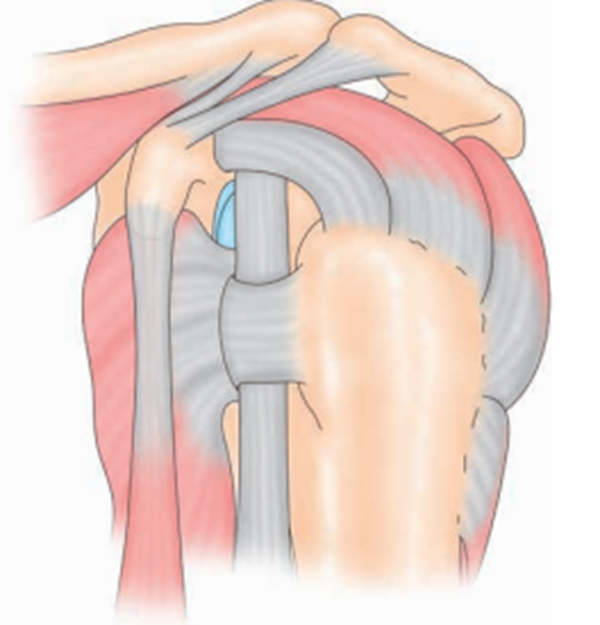

肩袖是由冈上肌、冈下肌、肩胛下肌和小圆肌4块肌肉的肌腱组成的一个袖套样结构,包绕肱骨头,止于肱骨的大、小结节(图1)。肩袖的肌肉在肩关节的正常生理活动中起重要的稳定和动力作用。

图1 肩袖结构